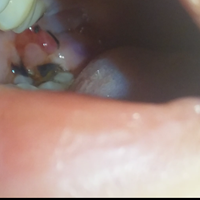

¿Qué es está bolita en mi encía?

Creo casi seguro que es una infección, acude a el cirujano maxilofacial.